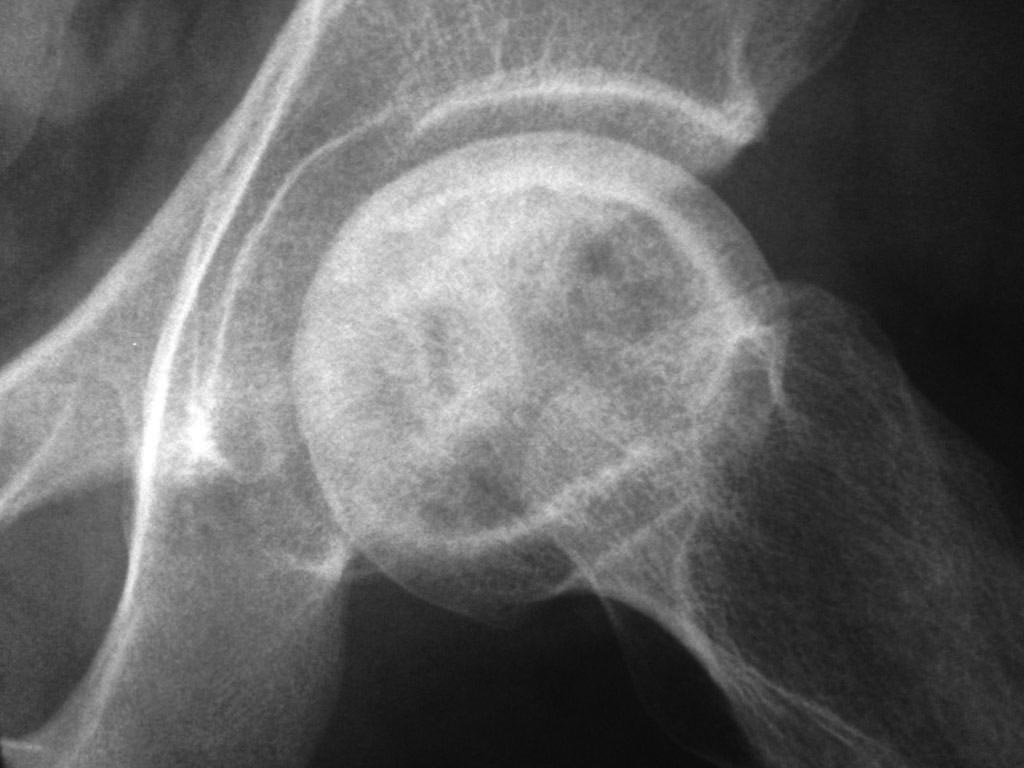

AVN. Синонимы: ишемический костный некроз, костный инфаркт, костный некроз, асептический некроз.

Возможно сомнения в диагностике связаны с нетипичной рентгенологической картиной. На снимке большая киста, которая расположена в центре головки, а при АВН начинается в верхней нагрузочной зоне. Отсутствует коллапс, сохранилась сферичность головки; не очень выраженный, но характерный признак "Crescent Sign".

Диффернциальную диагностику надо делать с доброкачественной кистой или метастазами. Но двухсторенная киста встречается очень редко, и киста в шейке распологается более дистально, чем при АВН. Гетерогенная картина головки немного напоминает метастаз, но без первичной опухоли и затяжной характер течения заболевания снимает подозрение на злокачественный процесс.

При наличии коллапса диагноз устанавить очень легко. Сканирование с изотопами тоже хороший метод исследования, который покажет "холодные" участки, окруженные "теплыми" зонами. Исследование в 25% дает погрешность, и поэтому на сегодня МРТ является "золотым стандартом" исследования. Пункция не помешает, но мне кажется, что здесь по классификации Ficat преколлапсный, т.е. вторая степень АВН.